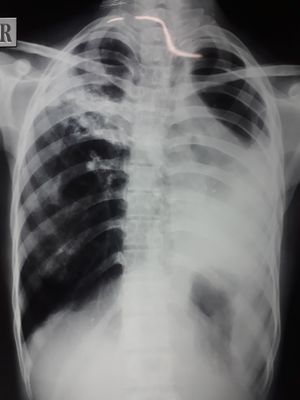

18 yr old female past h/o ATT FOR 9 months in childhood.now c/o cough breathlessness on exertion and fever since 1 month.

It could be hemothorax. Pyothorax. Sonography of thorax or ct scan can be helpful. And then tap the effusion inorder to diagnose the source of effusion.